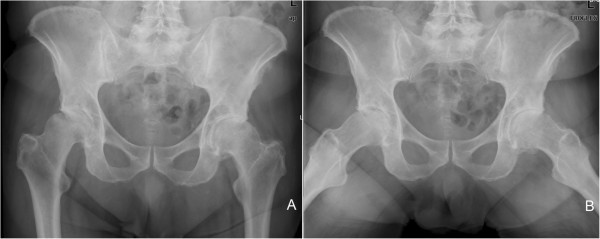

An Atypically Located Large Subchondral Cyst In An Osteoarthritic Hip

An atypically located large subchondral cyst in an osteoarthritic hip jmedicalcasereports.biomedcentral.com

cyst subchondral osteoarthritic atypically